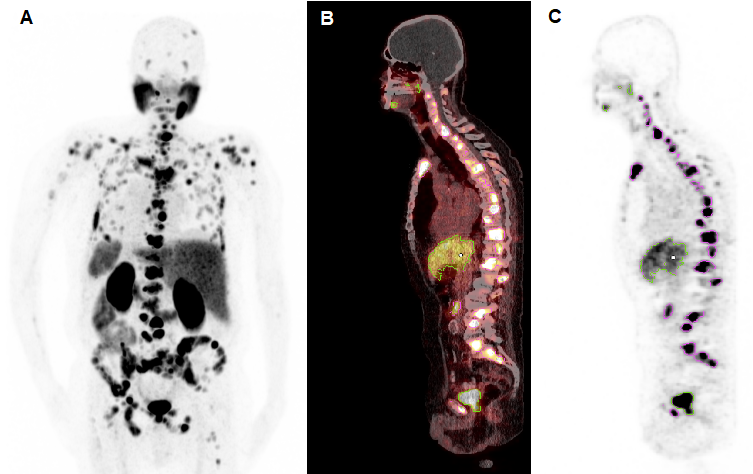

Figure 2

Representative example of semi-automatic tumour segmentation using Syngo.Via. (A) Maximum intensity projection of [68Ga]Ga-PSMA-11 PET/CT. (B) Sagittal slice of PET/CT fusion. (C) PET data with semi-automatically drawn volumes of interest (violet, tumour lesions; green, physiological uptake).

Molecular imaging-based response was assessed by calculating the whole-body total lesion PSMA (TLP) and molecular tumour volume (MTV) from [68Ga]Ga-PSMA-11 PET/CT collected before and after [225Ac]Ac-PSMA-617/[177Lu]Lu-PSMA-617 tandem therapy by applying a semi-automatic tumour segmentation using Syngo.Via (Enterprise VB 30, Siemens, Erlangen, Germany). For tumour segmentation, a standard uptake value (SUV) threshold of 3.0 was applied, in accordance with Ferdinandus et al. [27], except for liver metastases (in 2/17 patients), where an SUV threshold of 1.5 × SUVmean of the healthy liver tissue was applied. Physiological uptake in healthy organs was manually excluded. A representative example of the semi-automatic tumour segmentation is presented in Figure 2. TLP was calculated in analogy to total lesion glycolysis (TLG), which is an established parameter in [18F]FDG PET/CT for therapy monitoring [28], as the summed products of volume and uptake (SUVmean) of all lesions. TLP values are expressed as mL × SUV to distinguish them from MTV values, which are presented in mL. Between PET scans, androgen deprivation therapy (ADT) and therapy with next-generation androgen receptor signal inhibitors such as enzalutamide or abiraterone were continued unchanged to avoid altering PSMA expression [29] (ADT in 17/17, enzalutamide in 13/17, and abiraterone in 1/17 patients). As in other studies [30,31], the PET response criteria in solid tumours (PERCIST) version 1.0 [32] were slightly modified: partial remission was defined as a decrease in TLP or MTV of >30%, progression as an increase of >30% or development of new metastases, and stable disease as a change between ±30%.